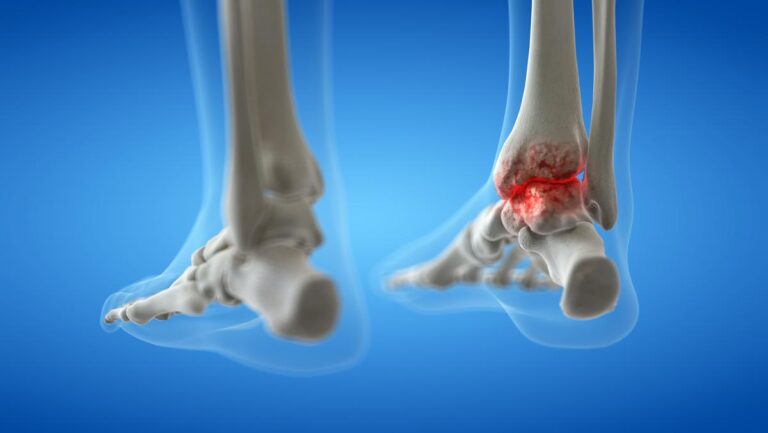

What is Ankle Fusion Surgery?

Ankle fusion surgery is a procedure that permanently fuses the bones of the ankle joint together to treat severe ankle arthritis or chronic instability. It aims to alleviate pain and improve stability but results in a loss of ankle motion.